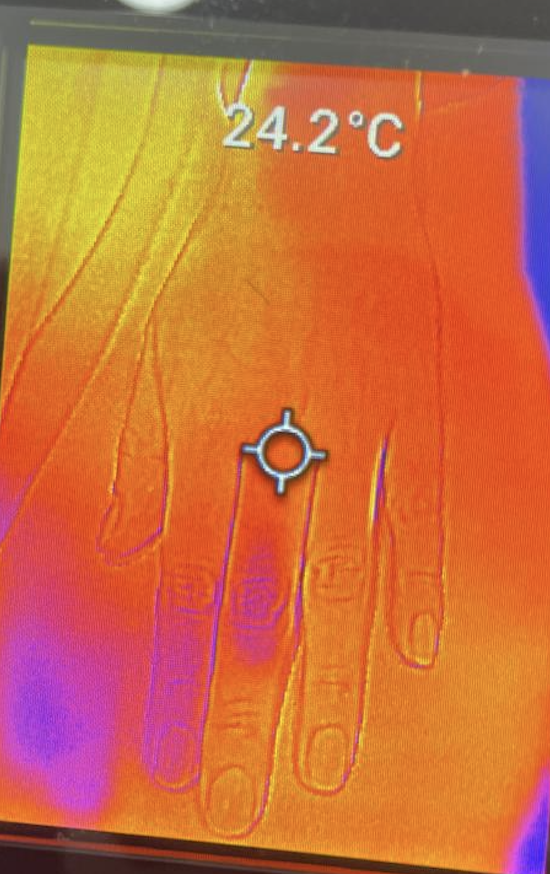

Dorso de la mano del control sano

Palma de la mano del control sano